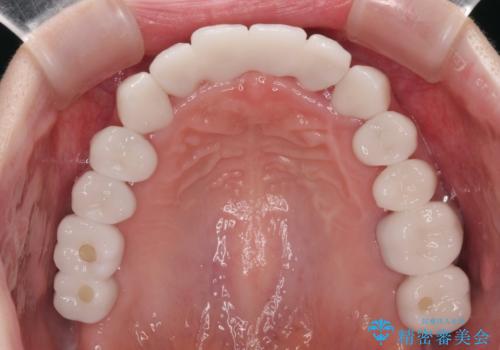

自他共に認める、非常に色白の患者様であったため、黄ばんだ歯の色を白くすることを希望されており、歯周病治療の該当部位に限らず、全顎的にオールセラミッククラウンにて補綴治療を行うこととしました。

多くの外科処置を行ったため、治療期間も長くなり、患者様の負担は非常に大きなものとなりましたが、明るく健康的な口元となり、患者様には大変満足していただけました。